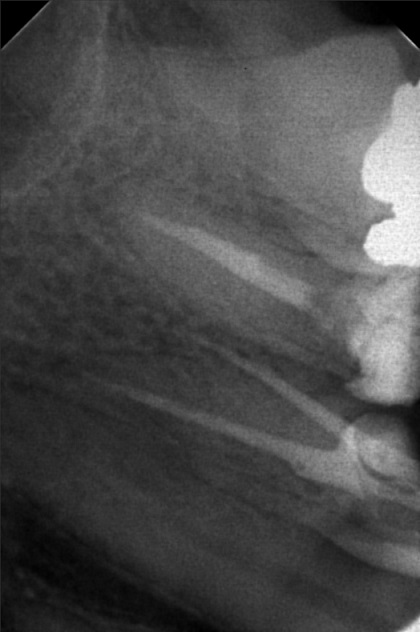

Edit Record Check our patient data records. Add patient information Patient Info Profile picture Last Name First Name Middle Name Birthdate Age Street Barangay City Country Zip Code Contact number Email Procedure > #25 buil-up w/fiber pero > 20mm obturation > xray > icf 09/03/22- open canal/ ML canal Eugenol/ Tf 9/10/10- MB #25 20mm, ML #30 20mm/ Camphenol, TF File sylvia_mariano.jpg File 2 sylvia_mariano_2.jpg File 3 sylvia_mariano_3.jpg File 4 sylvia_mariano_4.jpg File 5 File 6 File 7 File 8 File 9 File 10 File 11 File 12 File 13 File 14 File 15 File 16 File 17 File 18 File 19 File 20 Retain Record Retain Record Yes No Save Your Changes